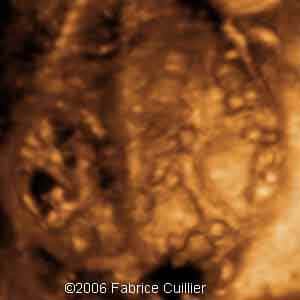

3D coronal view of the kidney at 19 weeks

7